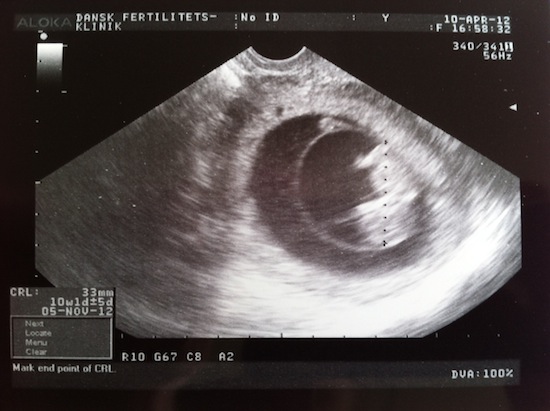

Vi har også været til to scanninger tidligere på grund af vores forhistorie. Det har vi været meget glade for, da det har givet lidt mere tryghed.

2. scanning 2. scanning - 10. april, 33,5mm